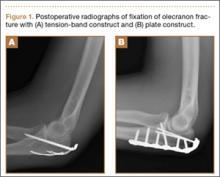

Olecranon fractures are a common injury, representing 10% of all upper extremity fractures.1 Displaced fractures require fixation to restore anatomical alignment and minimize posttraumatic arthrosis.2,3 Multiple surgical techniques have been developed to treat these fractures, with implant choice largely dictated by fracture pattern and associated injuries. Simple, noncomminuted, transverse, proximal fractures can be treated with a tension-band construct, and fractures that are comminuted, oblique, distal to the midpoint of the sigmoid notch, or associated with complex elbow injuries generally require locking-plate fixation.4,5 Although both tension bands and locking plates have been used successfully (Figures 1A, 1B), they remain some of the most frequently removed orthopedic implants, usually because of implant prominence.6